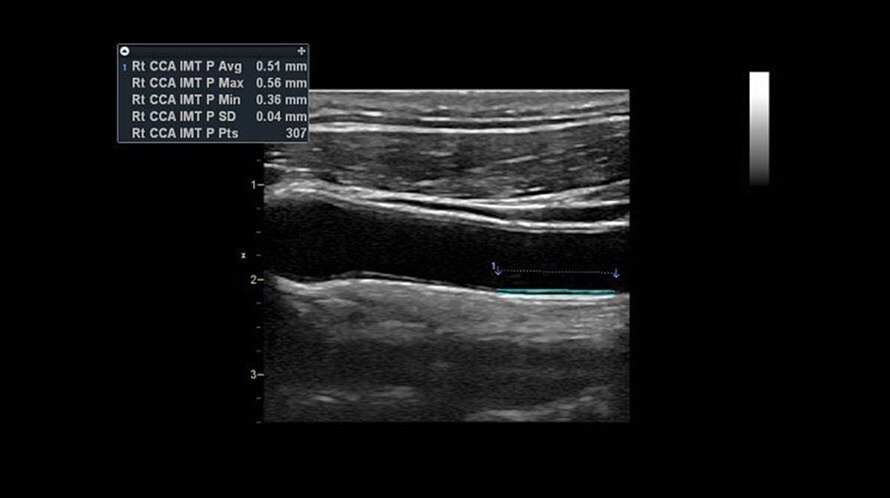

Auto IMT

Обеспечивает автоматическое определение границ и толщины комплекса интима-медиа и выполнение требуемых измерений.